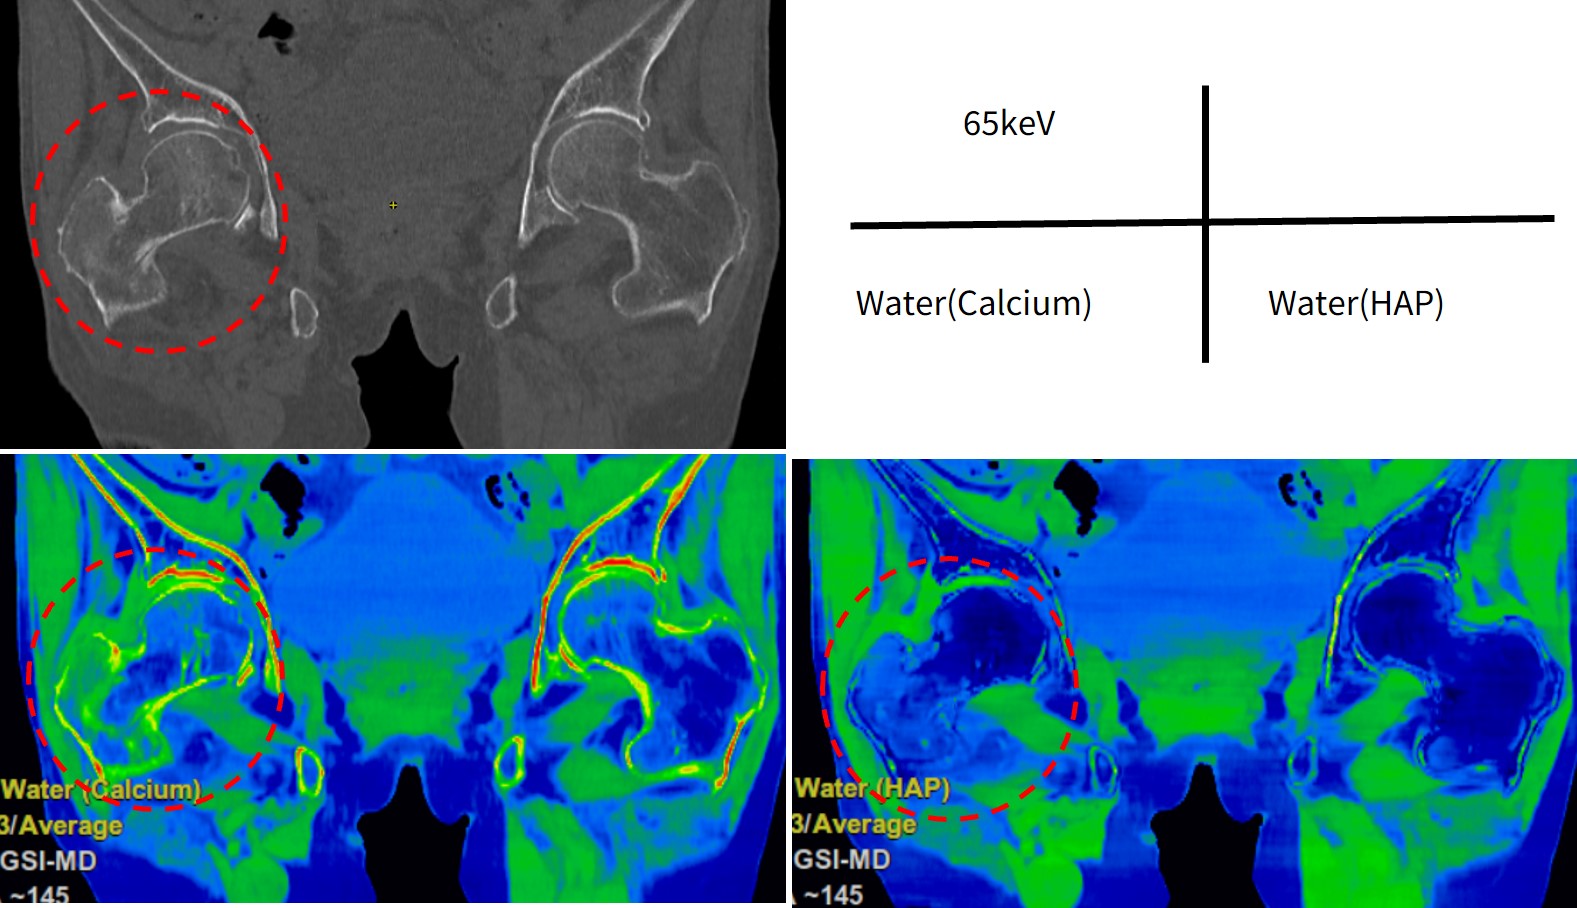

症例5)大腿骨転子部骨折

転倒し、右股関節痛のため歩行不能。右大腿骨大転子に圧痛あり、XPで骨折は不明瞭のためCTを行った。65keV画像では右大腿骨転子部に骨折が認められ、Water(Calcium)とWater(HAP)画像で骨髄浮腫が確認できた(Fig.7)。

revolutionapexelite_aomori11.jpg

Fig.7 Bone Marrowで骨髄浮腫が確認できた症例